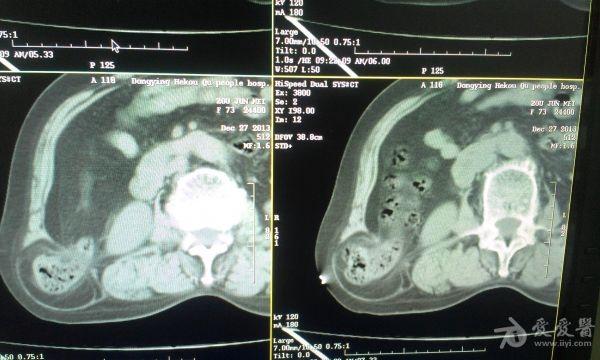

挺经典的腰疝

右腰部包块,随呼吸可运动。

非常经典的ct片,不知是继发于何种原因还是先天性的?里面内容物一般是肠管,很少发生较窄、嵌顿。